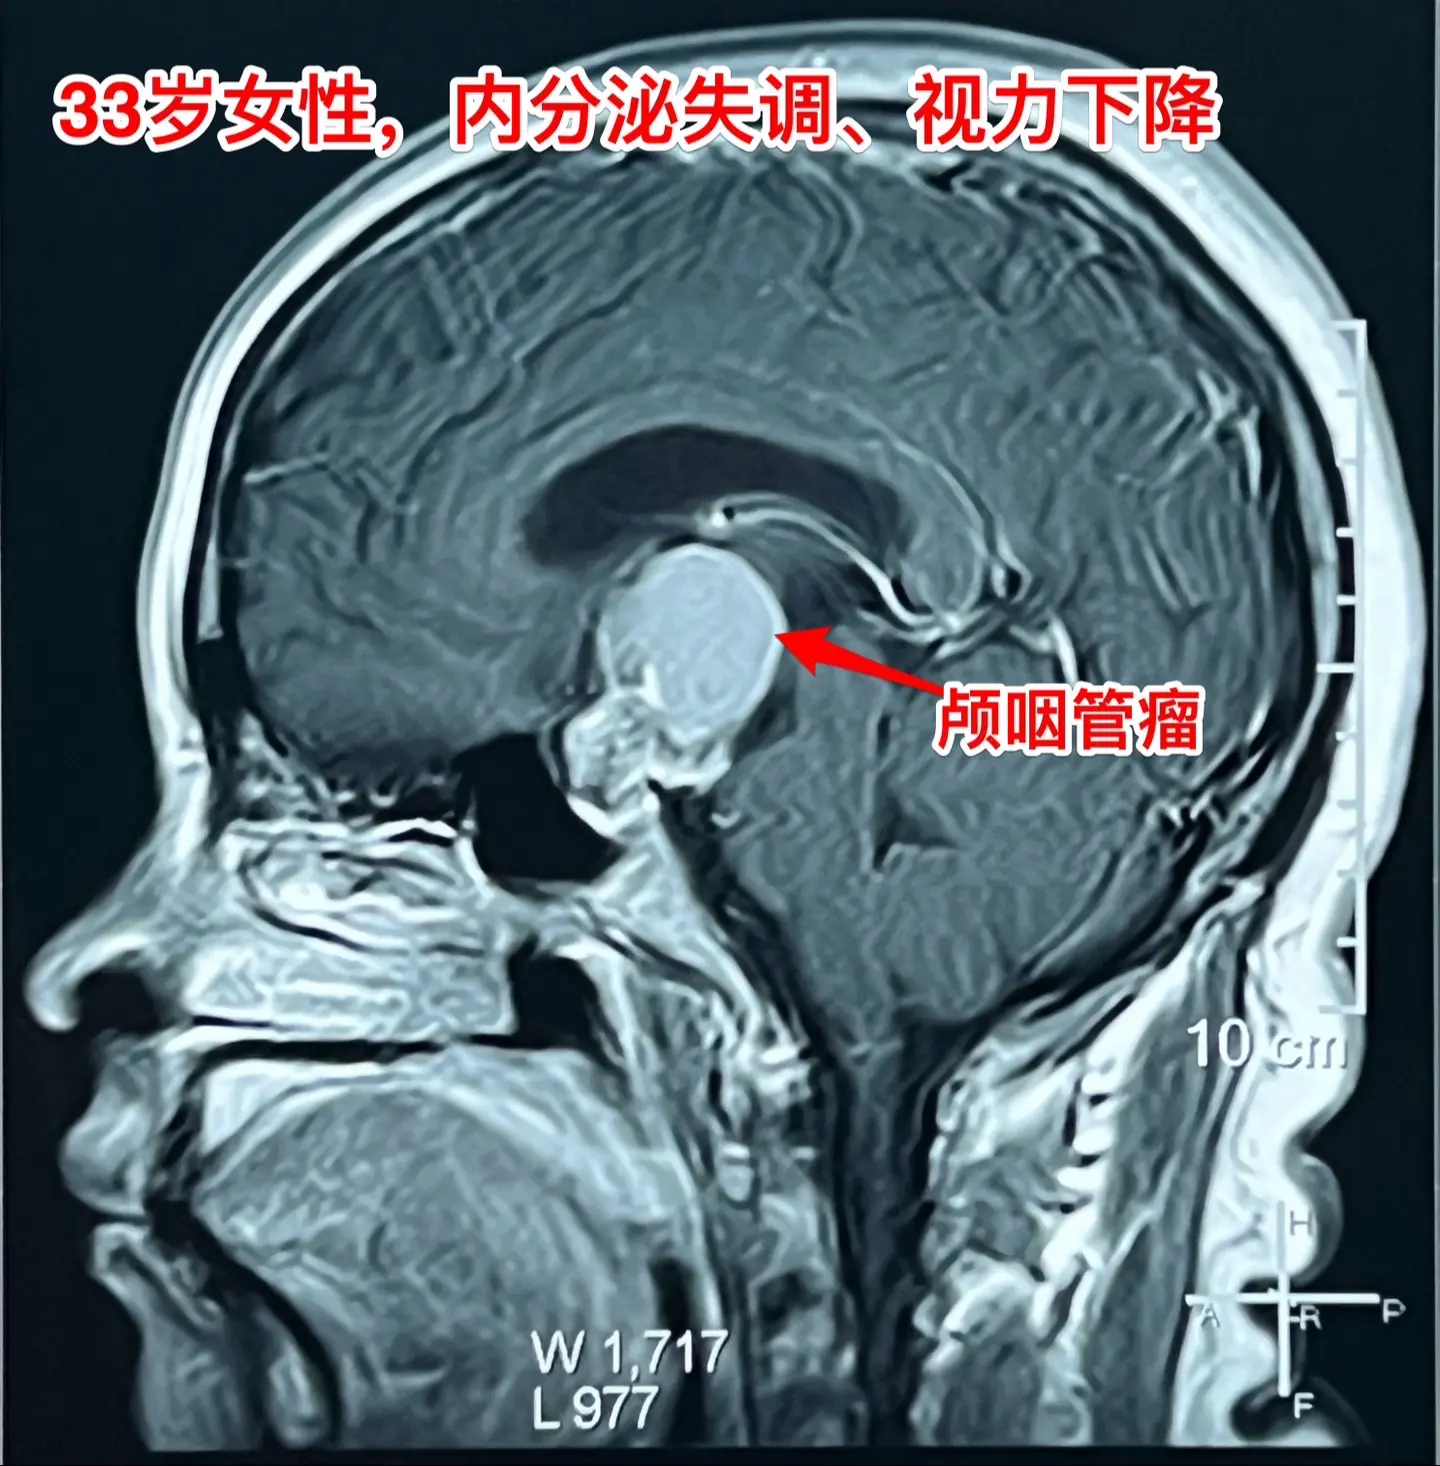

33岁颅咽管瘤患者终于下决心作手术了。洛阳市的女教师,2021年因内分泌紊乱到医院检查,就发现了颅咽管瘤。 由于对手术感到恐惧,再加上工作原因和其他原因,患者一直在观察中,未作手术。 她认识好几个曾经在我这里作过手术的颅咽管瘤病友,每一个成功的手术对她都是一次鼓励! 今年八月份患者和我联系了,说磁共振显示肿瘤在增大,有脑积水了,她也有多睡症状,视力有下降。所以她下定决心要来作手术。 10.28行开颅手术将肿瘤完全切除。肿瘤内有大块钙化,将肿瘤完全切除。手术后患者自述视力有好转。